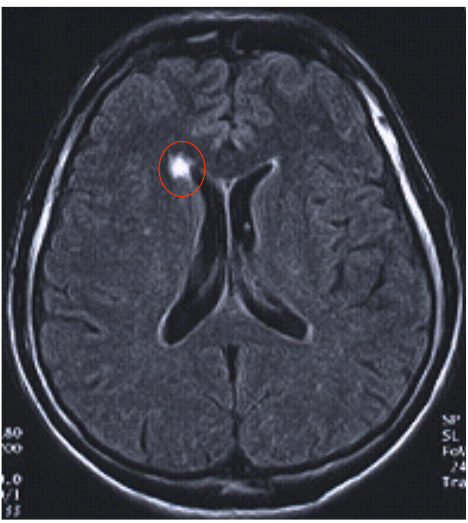

Comparaison T2 et T2 FLAIR A